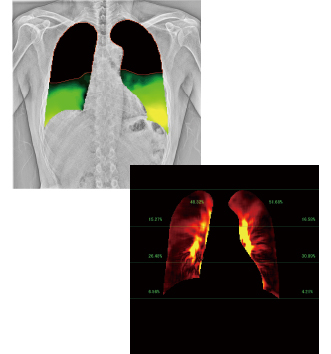

X線動画解析ワークステーション「KINOSIS」

単純X線撮影は静止画から動画へ。コニカミノルタは単純X線撮影の常識である従来の静止画撮影に加え動画撮影による新たな診断価値創出にチャレンジしています。X線動画解析ワークステーション「KINOIS」は臨床の現場で使用されることにより日々進化しています。動きの観察のしやすさを追求した新たな解析アルゴリズムの開発はさらなる診断価値の向上や生産性の向上につながると考えています。変革に挑み続ける当社の技術をご体験ください。